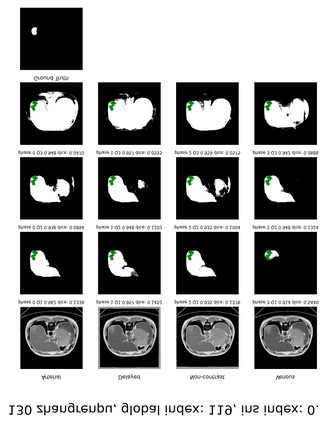

Learning to segmentation without large-scale samples is an inherent capability of human. Recently, Segment Anything Model (SAM) performs the significant zero-shot image segmentation, attracting considerable attention from the computer vision community. Here, we investigate the capability of SAM for medical image analysis, especially for multi-phase liver tumor segmentation (MPLiTS), in terms of prompts, data resolution, phases. Experimental results demonstrate that there might be a large gap between SAM and expected performance. Fortunately, the qualitative results show that SAM is a powerful annotation tool for the community of interactive medical image segmentation.